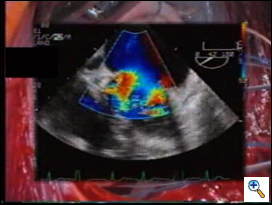

The best application of the edge-to-edge is when the valve is severely affected by myxomatous changes, with leaflet thickening, bileaflet significant prolapse and redundancy, multiple jets at Colour-Doppler TEE.

![]() |